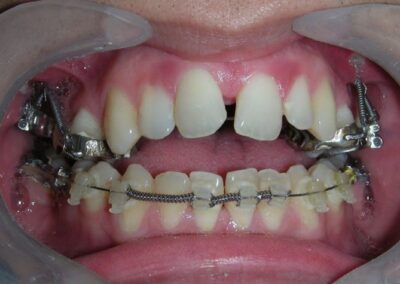

Was installed a Hyrax-type 10mm palatal expander of the Brazilian trademark Morelli® , modified by the author to be adapted to receive TADs microscrews, in order to initiate maxillary disjunction with MARPE (Mini-implant Assisted Rapid Palatal Expansion), TADS was installed with skeletal anchorage placed bilaterally having as references the roots of the maxillary canines and first premolars. Prior to insertion, local infiltrative anesthesia was administered using 2% lidocaine hydrochloride with 1:100,000 epinephrine. A total dose of approximately 0,8 mL per side (cortical infiltration technique). The TADs were inserted under aseptic conditions using a manual driver. Microscrew Evolution 1,6 Ø x 10 mm from the Argentine brand Odontit® . The Hyrax expander was then fitted and activated after 48 hrs .

Protocol of one activation per day was followed for a period of three weeks where the first clinical and radiographic evaluation was performed, showing clear signs of skeletal expansion, including the presence of a midline diastema. One more week of activations was added with a total of 28. The patient reported moderate headache during the first week of activation.

Having successfully achieved the expansion, we proceed to the intrusion of the posterior superior sectors, modifying the Hyrax by adding anchoring hooks at the buccal level of the first premolars. Using the Hyrax as anchorage, we sought a parallel intrusion. This could be replaced by a palatal bar. TADs were installed bilaterally at the mesial level of the first molars, inserting them as parallel as possible to the roots.

As the reader may infer, alignment and leveling of the upper anterior segment are being intentionally deferred at this stage of treatment. This strategic decision is based on the primary objective of closing the anterior open bite not through anterior extrusion, but by means of controlled posterior intrusion. This biomechanical approach promotes a counterclockwise rotation of the mandible, which leads to a increase in the facial axis angle and improvement in vertical facial proportions. By avoiding early anterior alignment, we prevent any premature vertical displacement of the upper incisors.